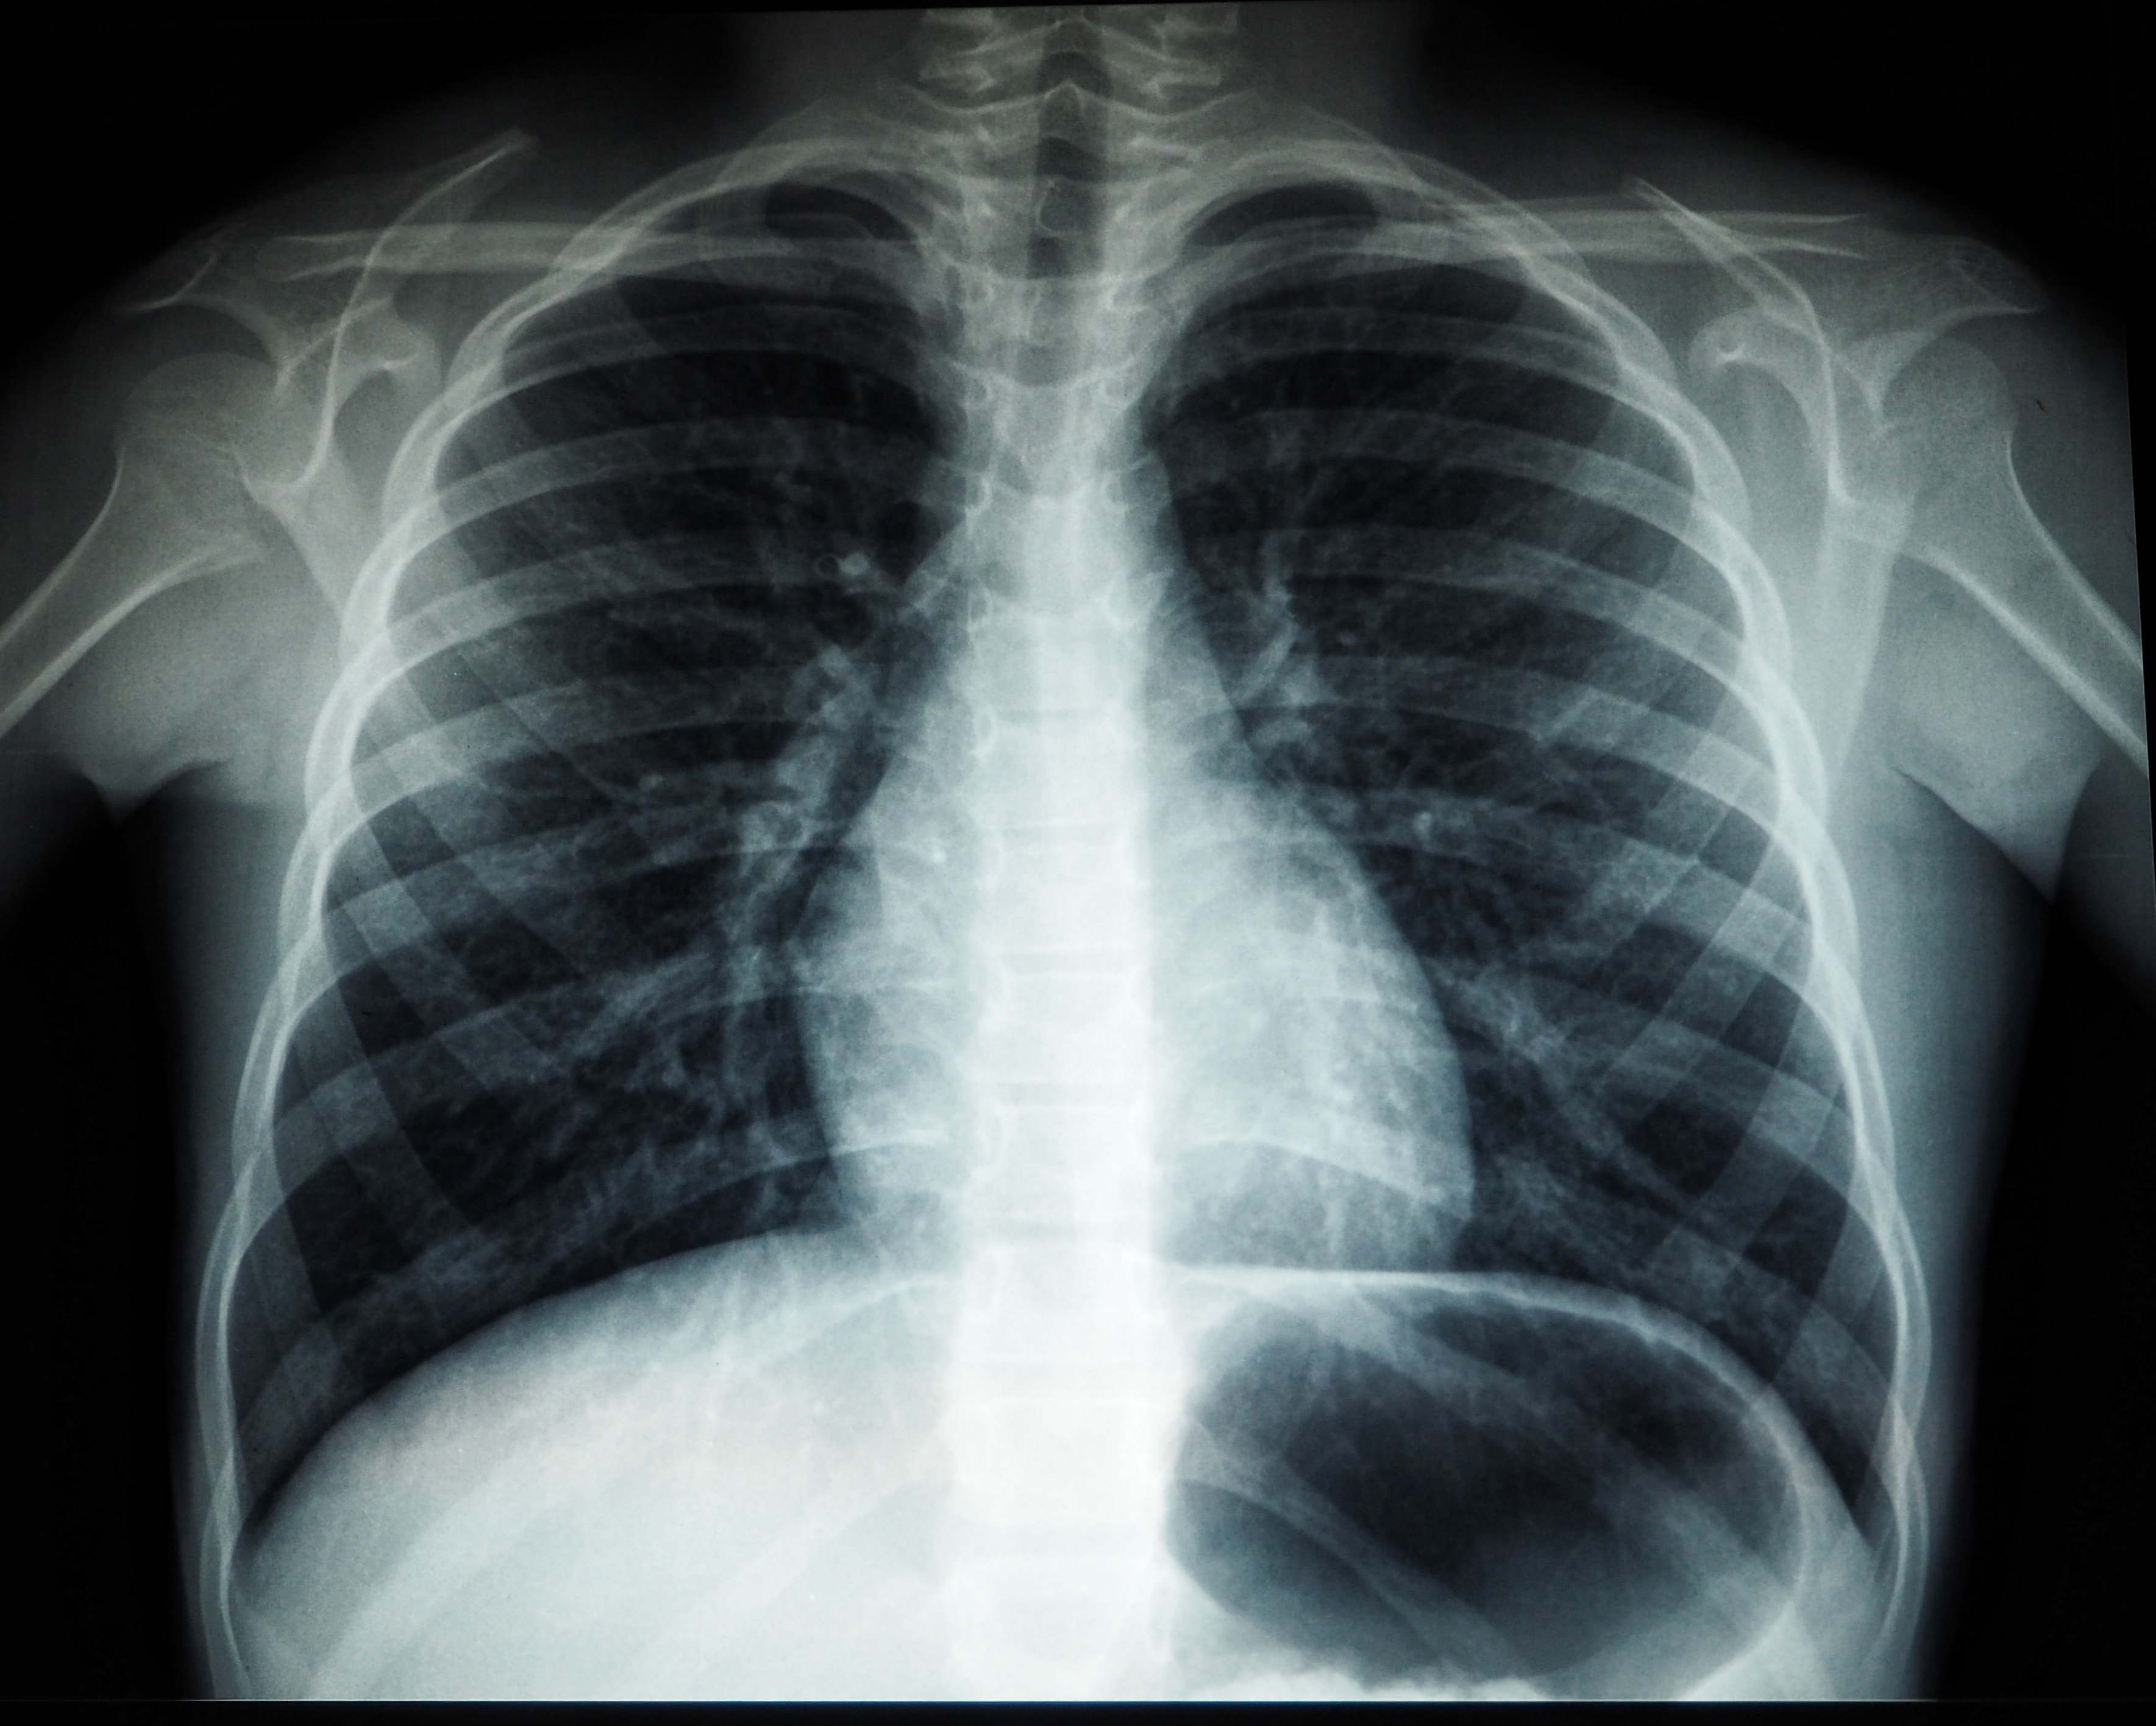

XenoView is a hyperpolarised contrast agent for use with magnetic resonance imaging (MRI) in evaluating lung ventilation in adult and paediatric patients aged 12 years and above. It enables visualisation of lung ventilation without exposing patients to ionising radiation and its associated risks. The Polarean HPX Hyperpolarisation System creates a dose of XenoView that is administered in a single 10 to 15 second breath hold MRI procedure.

Last week, the company revealed the first successful use of the newly approved technology, with a 19-year-old male with cystic fibrosis the first patient to be scanned at the Cincinnati Children's Hospital Medical Center in the US. Cincinnati expects to conduct more scans imminently, while Polarean plans to sell 15 to 20 polariser systems and 75 to 100 cylinders of XenoView by the end of 2024.